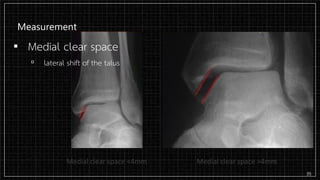

Measurement

▪ Medial clear space

▫ lateral shift of the talus

Measurement ▪ Medial clearspace ▫ lateral shift of the talus 35